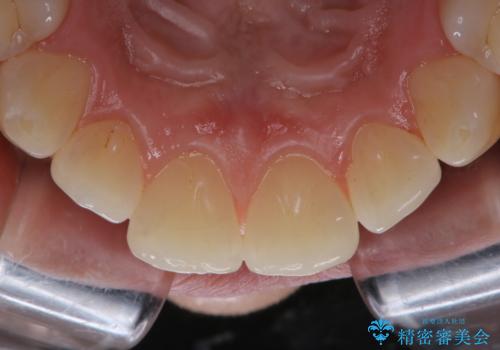

タバコによるヤニ、着色、歯の汚れをPMTC(60分コース)で除去。